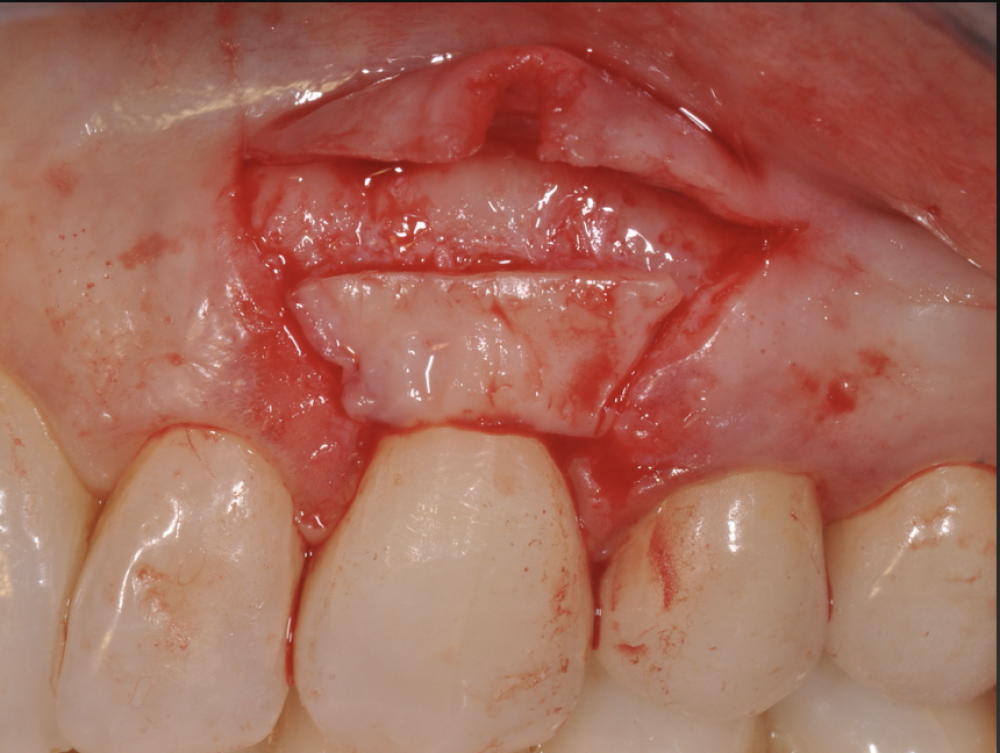

The Advanced Training Workshop on Soft Tissue Management and Treatment of Peri-implantitis is an interactive course aiming at clinicians wishing to upgrade their skills in the soft tissue management around implants to treat mucogingival deficiencies and in the application of non-surgical and surgical treatment to peri-implant diseases. The course consists of an integrated approach designed to build and extend the competence of the practicing periodontist in the area of contemporary mucogingival surgery, peri-implant surgery, microsurgery and minimally invasive surgery. The topics will be covered with lectures powered by 2D and 3D video demonstrations, case discussions, and focused hands-on training on animal and silicon models.